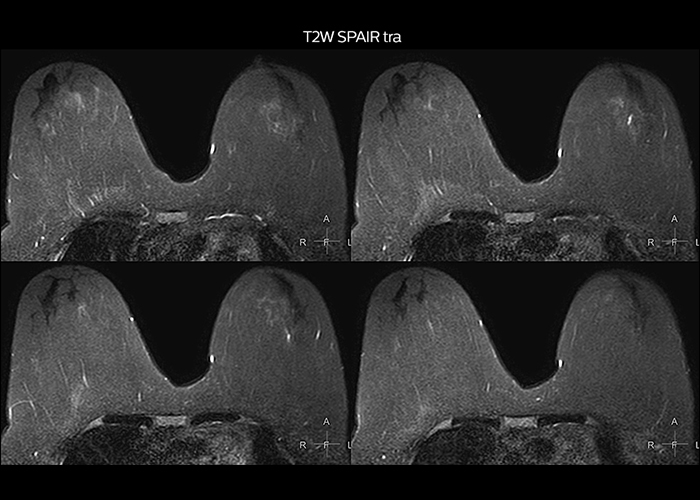

“On average, we scan about 80 patients per day, but on some days we scan well over 100 patients. The scanner is in use 7 days per week, operated 20 hours per day on week days and 8 hours per day in the weekend,” Mr. Tuna says. “To avoid coil changes we plan examinations of similar anatomies back to back, such as head and spine. Multiva helps us here a lot because coils don’t need to be changed frequently. Moreover, thanks to parallel imaging technology and 16-channel HeadSpineTorso and 8-channel MSK coils we are able to achieve excellent image quality. In this way Multiva helped us to increase both image quality and productivity.” “Neurological cases, such as brain and spine imaging, represent the largest share in our MR scanning, followed by musculoskeletal cases. In general, we use simple and basic imaging protocols. But occasionally, we use advanced techniques for problematic cases if necessary.

“Since we have Multiva, we have improved our workflow, because it has been so easy for our operators to learn and use Multiva. Our operators notice that the coils are lightweight and coils don’t need to be changed frequently. The user interface is easy to use. Features like this help us to scan a high number of patients. For instance, the musculoskeletal coils can be used interchangeably, and due to the user-friendly interface, the number of mistakes such as, for example, correct coil element selection has decreased significantly, because the system does it automatically by itself.” “Most important, Multiva satisfies our clinical imaging needs very well,” says Mr. Tuna. “Many features of Multiva have become similar to the Ingenia system. Even in more complex imaging such as abdominal and cardiac, the image quality and performance of Multiva is better than we expected. General surgeons and physicians from our hospital’s internal medicine department prefer to refer to us because of this.”

“Overall, Multiva provides what we need in term of patient needs and even potential needs,” says Mr. Tuna. “It allows us to scan a high patient volume and image a large variety of anatomies and conditions.” “Our goal is to achieve uncompromising quality based on universal standards, while solving clinically complex cases. Our Multiva scanner allows high productivity with fast imaging time, and allows us to make confident diagnoses in a broad range of cases.” “It’s an excellent multi-purpose scanner that satisfies all our MR imaging requirements in the hospital,” he concludes.